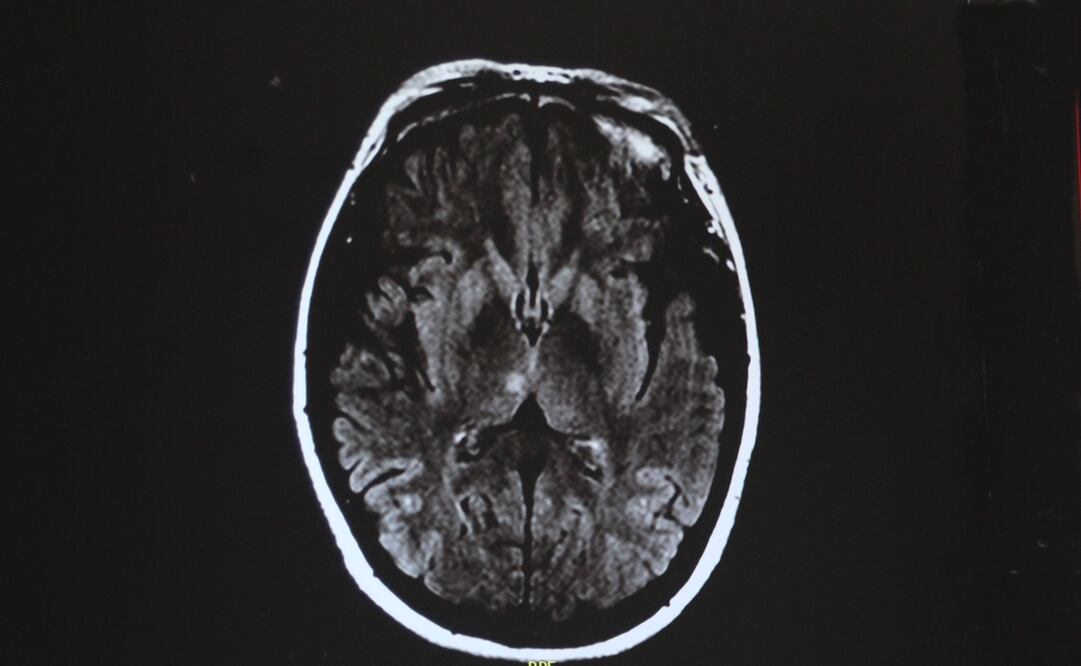

El proceso de curación de una lesión cerebral podría estimular el crecimiento de glioblastomas en ese órgano, un descubrimiento que puede abrir nuevas ideas sobre el tratamiento de este tipo de cáncer , según un estudio que publica este lunes Nature Cancer .

El estudio, que firman científicos canadienses y se centra en un cáncer cerebral común conocido como glioblastoma, indica que las nuevas células generadas para reemplazar a las perdidas por la lesión pueden sufrir cambios, lo que "podría estimular el crecimiento de un tumor".

Los expertos consideran que este descubrimiento podría conducir a nuevas terapias para los pacientes de glioblastoma, que actualmente tienen opciones de tratamiento limitadas con un promedio de vida de 15 meses después del diagnóstico, señala la Universidad de Toronto.

Dirks explicó que el glioblastoma puede considerarse "como una herida que nunca deja de curarse ", lo que ofrece una nueva perspectiva de cómo se origina y crece el tumor , y "abre ideas completamente nuevas sobre el tratamiento al centrarse en la respuesta de la lesión y la inflamación".

Los investigadores trazaron un mapa de la composición molecular de las células madre del glioblastoma (CMG), que el equipo había demostrado que son las responsables del inicio y la reaparición del tumor después del tratamiento.

Esto sugiere que "algunos glioblastomas comienzan a formarse cuando el proceso normal de curación de los tejidos , que genera nuevas células para reemplazar las perdidas por lesiones, se descarrila por mutaciones, posiblemente incluso muchos años antes de que los pacientes se vuelvan sintomáticos", dijo Dirks.

El equipo estudió GSC de tumores de 26 pacientes y analizaron casi 70 mil células con secuenciación de ARN unicelular , que detecta qué genes están activados en las células individuales.